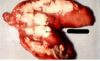

Vad syns på bilden?

- normalt/inte normalt

Till höger syns hypertrofi